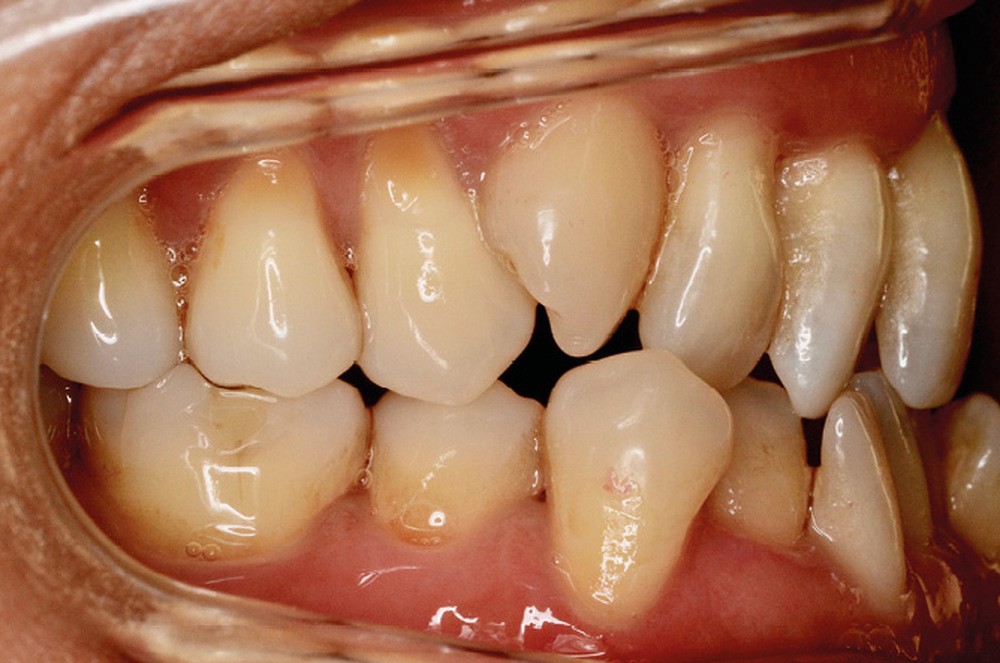

Sur le plan squelettique, on retrouve une classe III de Ballard par hypomaxillie, dans un schéma facial hyperdivergent.

Sur le plan dentaire, la patiente est en classe III droite et gauche, canine et molaire de 6 mm, avec une occlusion inversée antérieure localisée à 11, 12 et 22. Elle présente une dysharmonie dents-arcades sévère, une agénésie d’une incisive mandibulaire est à signaler, et les troisièmes molaires ont été extraites à l’âge de 21 ans.

Au niveau fonctionnel, on note un bruxisme statique avec contact permanent entre les dents maxillaires et mandibulaires. La patiente présente des prématurités en relation centrée sur les incisives, le guidage en propulsion est perturbé et des interférences multiples sont retrouvées en latéralités droite et gauche.